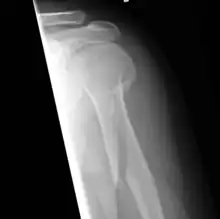

Fractura espiroidea

En medicina y traumatología, se designa con el nombre de fractura espiroidea a aquella fractura ósea en la cual la línea de fractura sigue una dirección espiral en relación con el eje principal o longitudinal del hueso. Se llama en ocasiones fractura por torsión en base al mecanismo de producción. Afecta fundamentalmente a los huesos largos como el húmero y la tibia.[1]

Las fracturas espiroideas se producen como consecuencia de la aplicación de una torsión sobre el hueso, de tal forma que una fuerza tiene un sentido y otra el sentido contrario, el hueso tiende a retorcerse sobre sí mismo hasta que la fuerza aplicada supera su resistencia elástica, produciéndose una línea de fractura que tiene un trayecto espiral. La torsión se define como la deformación que sufre un objeto, en nuestro caso un hueso, como consecuencia de una fuerza que le imprime un movimiento de rotación sobre su eje, estando un extremo fijo. Este mecanismo explica claramente la fractura de tibia por torsión en las que la pierna gira sobre sí misma, permaneciendo el pie inmóvil sobre el suelo.